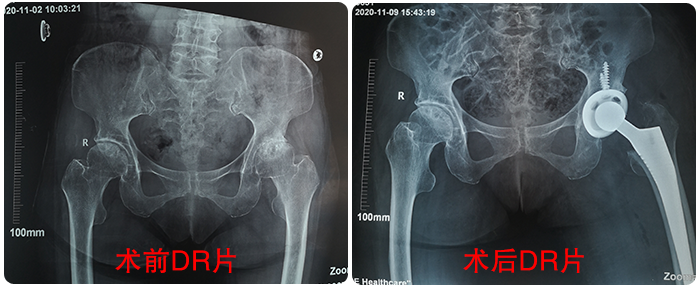

患者王女(nǚ)士現(xiàn)年(nián)63歲,今♥ ✘年(nián)5月(yuè)自(zì)覺雙側髋部疼痛,活∞✘≤"動受到(dào)了(le)限制(zhì)。11月(yu≤α<è)3日(rì)左側髋關節疼痛難忍,不(bù)敢活動,便來(l♦↑©™ái)院就(jiù)診,經查診斷為(wèi)“雙側股骨頭無菌性壞死”。11月(yuè)5日(r ←♥ì),為(wèi)其成功實施了(le)“左側人(rén)工(gōng)全髋關↔₽節置換術(shù)”。

王女(nǚ)士術(shù)前術(shù)後對(duì)比β↑☆γ影(yǐng)像患者萬女(nǚ)士現(xiàn)年(nián)56歲,7年(nián)前感覺雙↕↔₩側髋關節疼痛,近(jìn)4年(nián)來(lái)疼痛↕γσ的(de)越加強烈,雙膝無法伸直,無法正常走路(lùα<↓')。2019年(nián)5月(yuè)22日(rì)萬女(nǚ)士來(lái)到(dào)™我院就(jiù)診,經門(mén)診檢查後診斷為(wèi)“雙 ↑ε側股骨頭無菌性壞死”,實行(xíng)了(le)”右人(rén)♥$←工(gōng)全髋關節置換術(shù)”。今年(nián)11月(yuè)3日(rì),患者再次δ∑來(lái)到(dào)我院要(yào)求行(xíng)“左側人(rén♠')工(gōng)全髋關節置換術(shù)”。本月(yuè)5日(rì),完成手術λ₩(shù)。

患者王女(nǚ)士現(xiàn)年(nián)63歲,今年(nián)®↓5月(yuè)自(zì)覺雙側髋部疼痛,活動受到(dà•♠πo)了(le)限制(zhì)。11月(yuè)3日(rì)左側髋關節疼痛難忍,不↔×≤(bù)敢活動,便來(lái)院就(jiù)診,經查診斷為(wèi)“雙側股骨頭無菌性÷壞死”。11月(yuè)5日(rì),為(wèi)其成功實施了(le)“≤φ左側人(rén)工(gōng)全髋關節置換術(shù)”。

王女(nǚ)士術(shù)前術(shù)後對(duì)比影(yǐng÷÷)像患者萬女(nǚ)士現(xiàn)年(nián)56歲,Ω≠7年(nián)前感覺雙側髋關節疼痛,近(jìn)4年(nián)來(lái)疼痛← ↕的(de)越加強烈,雙膝無法伸直,無法正常走路(lù)。2019年(nián)5月<ε×(yuè)22日(rì)萬女(nǚ)士來(lái)到(dào)我院就(jiù"©)診,經門(mén)診檢查後診斷為(wèi)“雙側股骨頭無菌性壞死”,實行(xíng)了(l"♣e)”右人(rén)工(gōng)全髋關節置換術(shù)”∏ ∑。今年(nián)11月(yuè)3日(rì),患者再次來(lái)到(ε✘αdào)我院要(yào)求行(xíng)“左側人(rén)工(gōng)全髋關節置換術(sγ©<★hù)”。本月(yuè)5日(rì),完成手術(shù)。